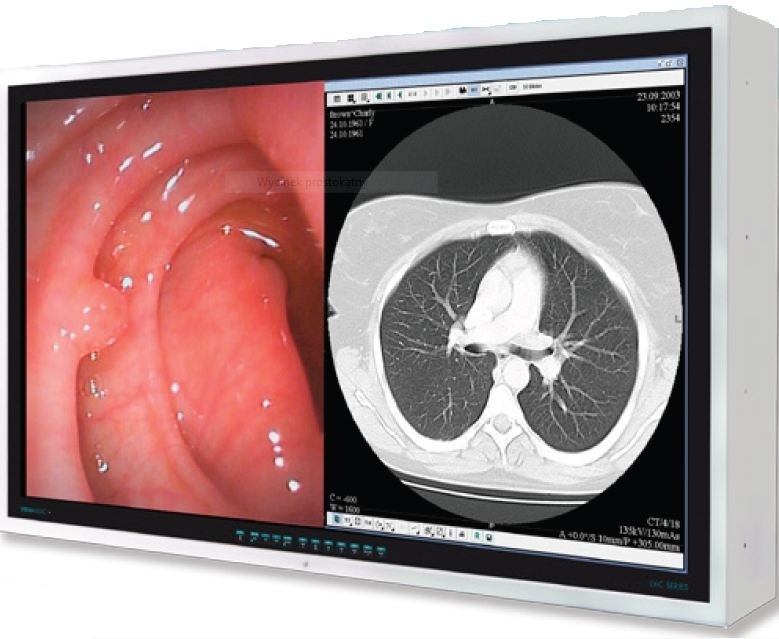

42” monitory medyczne VIEWMEDIC LV-C na bloki operacyjne

Wyświetlacze wielkoformatowe 42" VIEWMEDIC LV-C zostały zaprojektowane specjalnie z myślą o zastosowaniu w bardzo wymagających obszarach szpitalnych, takich jak sale operacyjne, oddziały intensywnej terapii i oddziały ratunkowe. Charakteryzują się one higieniczną obudową pokrytą powłoką bakteriobójczą oraz najwyższą na rynku w swojej kategorii klasą szczelności przed zanieczyszczeniami i zalaniem – IP65.

W związku z różnorodnymi wymaganiami stawianymi przed tego typu wyświetlaczami monitory LV-C są wyposażone w matrycę P-MVA do wyświetlania ruchomych sekwencji z bardzo krótkim czasem odświeżania obrazu 4,5 ms.

- 42” wyświetlacz LCD w rozdzielczości FullHD (1920 x 1080)

- Wejścia Video HDMI, DVI-D, VGA, CVBS, YPbPr/RGBS, S-Video, DICOM, oraz złącze przelotowe In/Out 3G-HD-SDI (opcja)

Możliwość wyświetlania jednocześnie dwóch niezależnych obrazów PiP (jeden obraz w drugim) i PoP (jeden obraz obok drugiego). Istnieje możliwość niezależnej konfiguracji parametrów (jasność, kontrast, etc.) każdego z wyświetlanych obrazów.